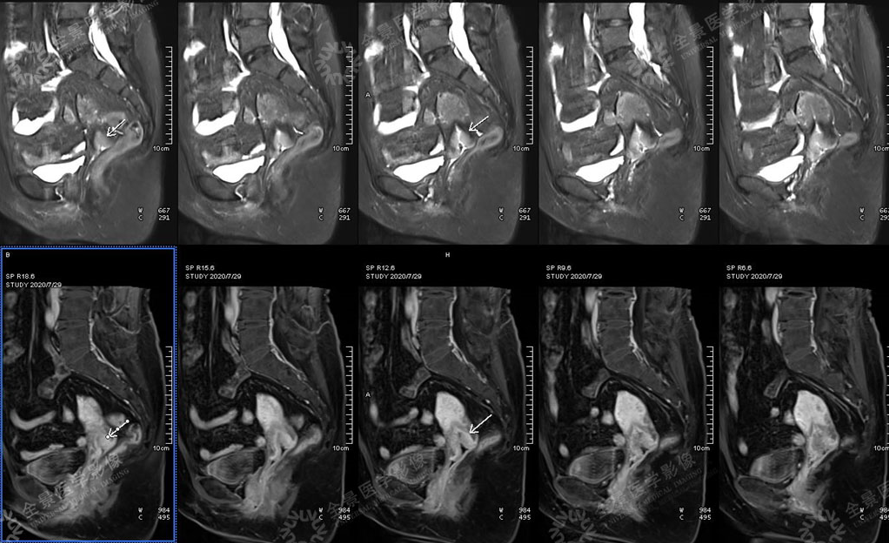

畸胎瘤

√MR显示病灶与脊髓的关系,压脂序列呈低信号;

√CT可显示病灶内钙化,可见少许脂肪密度;